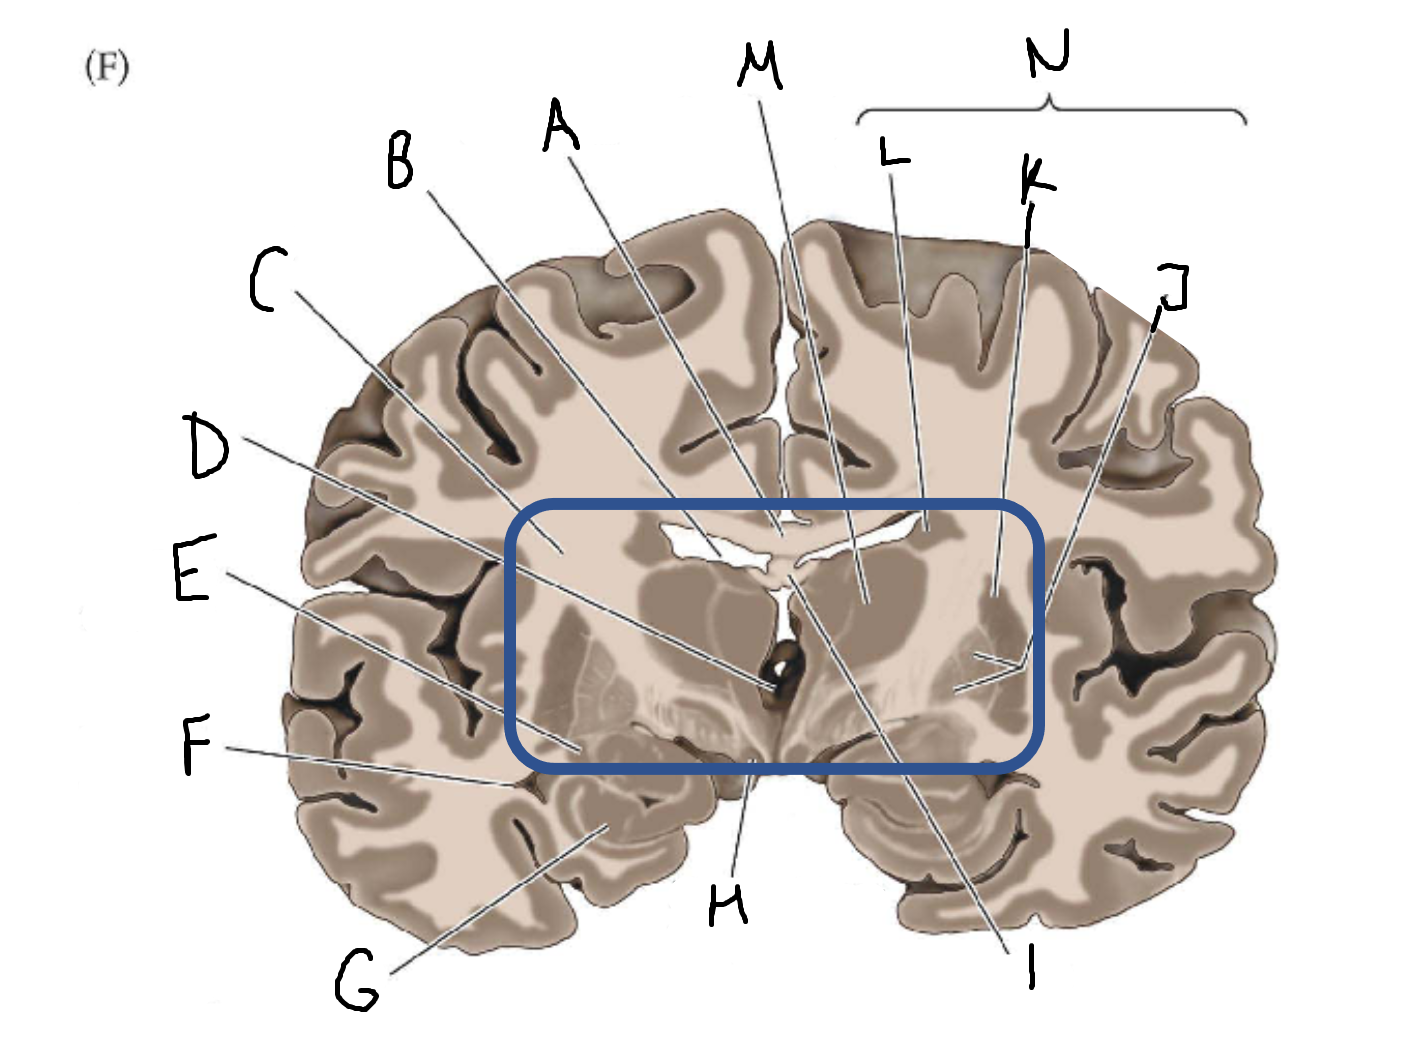

A

corpus callosum

B

lateral ventricle

C

internal capsule

D

third ventricle

E

tail of caudate nucleus

F

lateral ventricle

G

hippocampus

H

mammillary body

I

fornix

J

globus pallidus

K

putamen

L

caudate

M

thalamus

N

basal ganglia